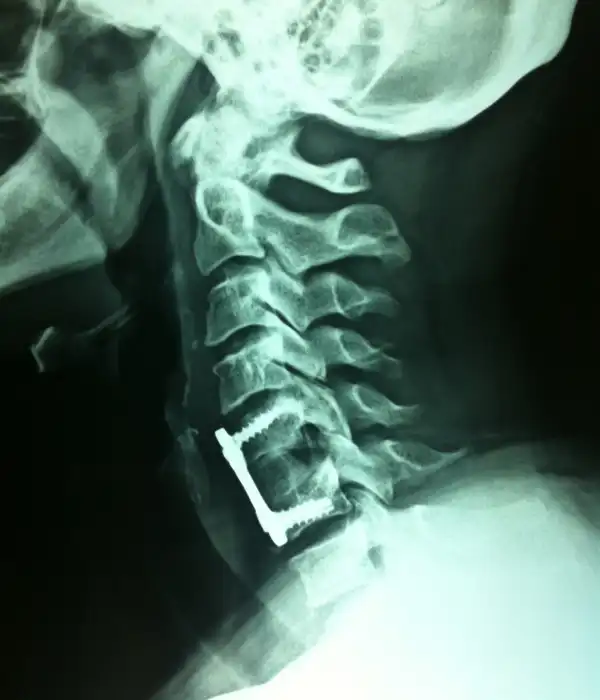

Anterior Cervical Discectomy Fusion

Anterior Cervical Discectomy

C1-C2 instability Post OP X ray

C1-C2 fusion Post OP X ray